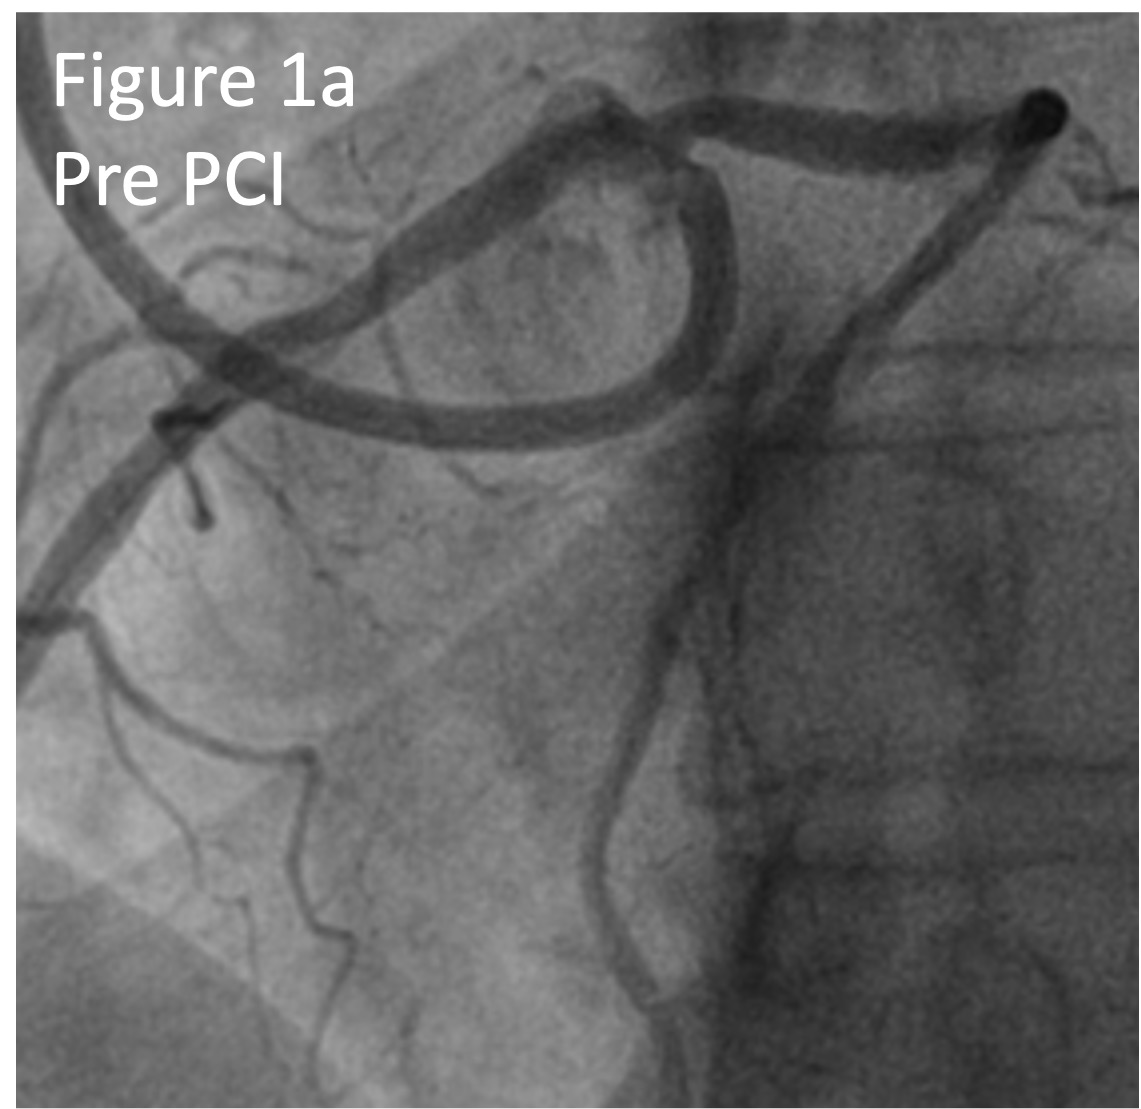

On representation a diagnostic coronary angiogram demonstrated a patent Left Main to Left Anterior Descending artery stent and severe stenosis in the ostial anomalous RCA (Figure 1a).

Intravascular ultrasound (IVUS) demonstrated severe ostial disease with a ¡°slit-like¡± appearance and a minimal luminal area (MLA) of 1.36mm2 (Figure 2a) with dynamic compression of the proximal RCA. The fibrotic RCA ostium was treated with a 3.5mm Wolverine Cutting Balloon. Real-Time IVUS ostial stenting was performed with a 3.5 x 16mm Megatron deployed. Post stent IVUS showed persistent dynamic compression at the ostium with a minimal stent area (MSA) of 6.53mm2 (Figure 2b). A 2nd 3.5 x 12mm Megatron was deployed over the 1st stent and post dilated with a 4.0 NC balloon to enhance its radial strength. Final IVUS showed minimal stent compression with an MSA of 8.1mm2 (Figure 2c). Final angiogram showed TIMI 3 flow (Figure 1b).